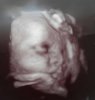

Super wieściMy po usg

Dawid waży 1806 gramów około i wszystko jest dobrze![]()

Ułożony już glowkowo